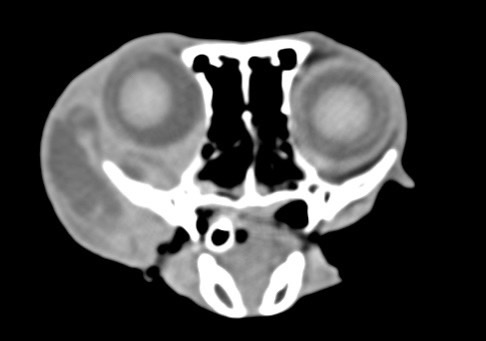

狗狗後腳癱瘓也有可能是血栓 不一定是骨骼神經肌肉問題喔

後肢癱瘓的柴柴經由他院轉診來築心做電腦斷層掃瞄因為狗狗以前病史有椎間盤突出問題

所以以為是脊椎問題想要來評估手術

掃瞄結果診斷為動脈血栓造成

主動脈血栓栓塞是一種急性且危及生命的疾病,當血液凝塊從心臟或其他部位脫落,經過血液循環流向並卡住動脈中的某些血管,造成局部的血液供應中斷、相應部位的器官或組織缺氧,將引起疼痛、損傷甚至壞死。

此患犬在電腦斷層影像以及後續追蹤的超音波下都可見明顯血栓影像